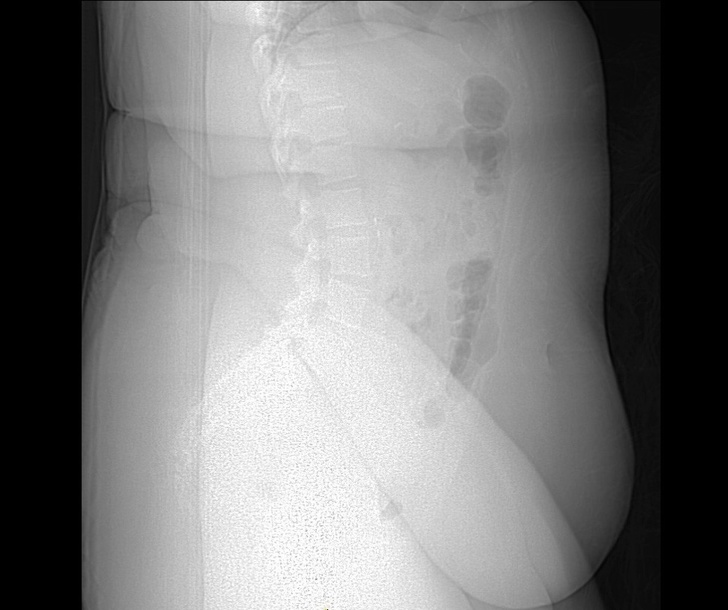

3. Röntgenová snímka osoby trpiacej obezitou. Prebytočné mäkké tkanivo sťažuje zobrazenie kostí